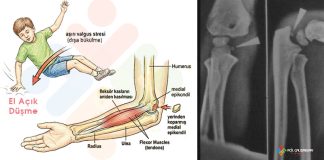

Medial epikondil kopma kırığı, 9–14 yaş arası çocuk ve adolesanlarda en sık görülen dirsek yaralanmalarından biridir. Özellikle beyzbol, hentbol, yüzme, cimnastik gibi valgus stresinin...